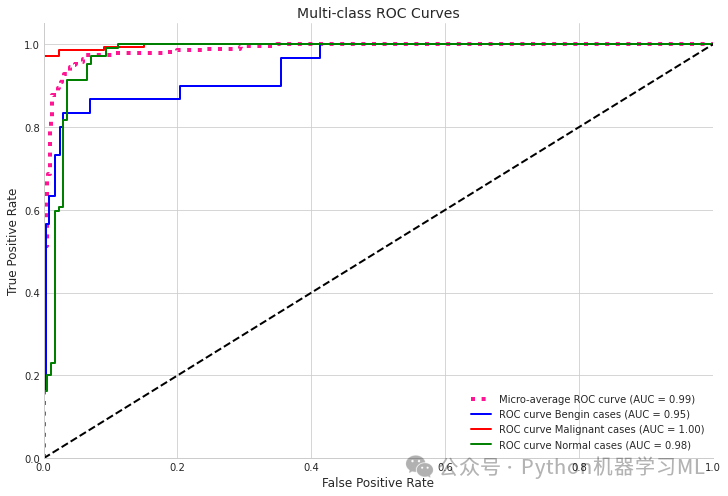

本文介绍了一种名为Lung-EffNet的新型转移学习预测器,它基于EfficientNet架构,通过添加顶层分类头进行修改。该模型在“IQ-OTH/NCCD”数据集上进行了评估,该数据集将肺癌患者分为良性、恶性或正常三类。研究使用五种不同的EfficientNet变体(B0-B4),并通过数据增强方法解决类别不平衡问题。Lung-EffNet在测试集上达到了99.10%的准确率和0.97至0.99的ROC分数,优于其他预训练CNN架构。EfficientNetB1因其高准确性和效率,以及较少的训练参数,成为临床环境中大规模部署的理想选择。

本研究提出了一种基于EfficientNetB1的转移学习方法,用于从CT扫描图像中对肺癌进行分类。该方法利用从大规模自然图像数据集中学习到的知识,显著减少了训练所需的计算资源和时间,同时保持了高水平的准确性。实验结果表明,EfficientNetB1在准确性和效率方面优于其他CNN架构,实现了99.10%的准确率和0.97至0.99的ROC分数。尽管该方法表现出色,但仍存在局限性,例如数据集规模和多样性不足。未来的研究方向包括探索其他深度学习架构、纳入更多临床数据以及在更大的数据集上应用EfficientNets的转移学习。

将详细解析一段用于多类分类模型评估的代码,代码主要包括ROC曲线绘制、混淆矩阵可视化、各项指标计算以及Grad-CAM模型解释等内容。将按照不同功能模块依次进行详细讲解。

第一阶段:ROC曲线与AUC计算

# 1. ROC Curve and AUC calculationfrom sklearn.metrics import roc_curve, auc, roc_auc_scorefrom scipy import interpfrom itertools import cycle

# Calculate ROC curves for multi-class problemy_pred_proba = model3.predict(X_valid)n_classes = 3

# Calculate ROC curve and ROC area for each classfpr = dict()tpr = dict()roc_auc = dict()

for i in range(n_classes): # Convert validation labels to one-hot encoding y_valid_bin = np.zeros((len(y_valid), n_classes)) for j in range(len(y_valid)): y_valid_bin[j, y_valid[j]] = 1

fpr[i], tpr[i], _ = roc_curve(y_valid_bin[:, i], y_pred_proba[:, i]) roc_auc[i] = auc(fpr[i], tpr[i])

# Calculate micro-average ROC curve and ROC areafpr["micro"], tpr["micro"], _ = roc_curve(y_valid_bin.ravel(), y_pred_proba.ravel())roc_auc["micro"] = auc(fpr["micro"], tpr["micro"])

# Plot all ROC curvesplt.figure(figsize=(12, 8))plt.plot(fpr["micro"], tpr["micro"], label=f'Micro-average ROC curve (AUC = {roc_auc["micro"]:.2f})', color='deeppink', linestyle=':', linewidth=4)

colors = cycle(['blue', 'red', 'green'])for i, color in zip(range(n_classes), colors): plt.plot(fpr[i], tpr[i], color=color, lw=2, label=f'ROC curve {categories[i]} (AUC = {roc_auc[i]:.2f})')

plt.plot([0, 1], [0, 1], 'k--', lw=2)plt.xlim([0.0, 1.0])plt.ylim([0.0, 1.05])plt.xlabel('False Positive Rate')plt.ylabel('True Positive Rate')plt.title('Multi-class ROC Curves')plt.legend(loc="lower right")plt.grid(True)plt.show()

=== Model Performance Summary ===Micro-average AUC: 0.9873Class average AUC: 0.9739Micro-average Precision-Recall Area: 0.9762

Class: Bengin casesAUC: 0.9471Precision: 0.9375Recall: 0.5000F1-Score: 0.6522

Class: Malignant casesAUC: 0.9980Precision: 0.9928Recall: 0.9716F1-Score: 0.9821

Class: Normal casesAUC: 0.9766Precision: 0.8512Recall: 0.9904F1-Score: 0.9156